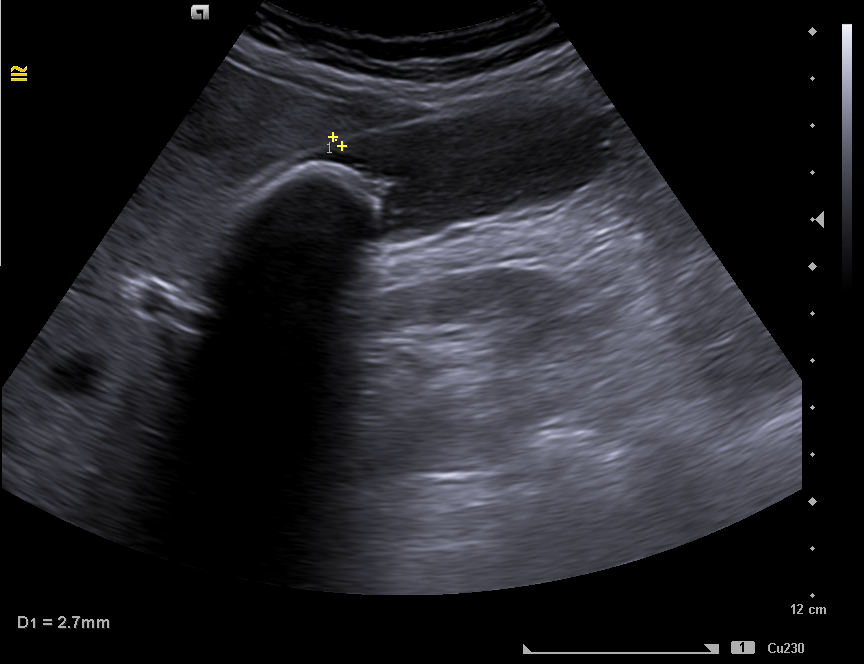

Se realiza una ecografía clínica en el momento, con calcificación en toda la vesícula, enfocando el diagnóstico en la presencia de una vesícula en porcelana y explicamos a la paciente el posible manejo.

Ante la clínica se cita a la paciente en ayunas, para conseguir una máxima distensión de la vesícula.  Se observa una imagen hiperecogénica  móvil, con sombra acústica posterior compatible con litiasis de 35 mm. Sin colección perivesicular ni dilatación de la vía biliar intrahepática y extrahepática. Hígado con ecoestructura y ecogenicidad normal, sin LOES en su interior.  Hallazgos compatibles con litiasis vesicular gigante, descartando el diagnóstico de vesícula en porcelana.